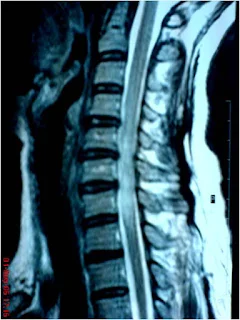

- Berdasarkan organ yang diperiksa seperti head and neck, spine (MRI myelography), musculoskeletal, sistem vaskular, thorax, abdomen, pelvis

![]() |

| MRI Lumbal |